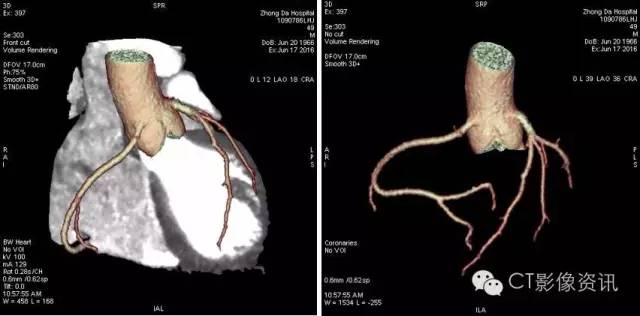

病例2:男性,49岁,BMI值26.4,冠状动脉CT成像与心肌灌注检查,只需一次打药,Revolution即可完成形态学和功能学检查。

CCTA及血管分析如下: